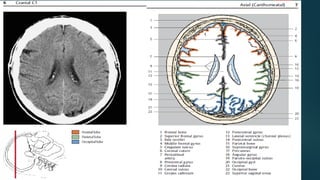

Este documento es el programa para un taller de imágenes del curso de emergencia 2015 impartido por el Dr. Víctor Delgado. El taller se centra en el uso de imágenes médicas para el diagnóstico y tratamiento de pacientes en coma traumático según la base de datos de Marshall. El Dr. Delgado es el único instructor repetido a lo largo del documento.